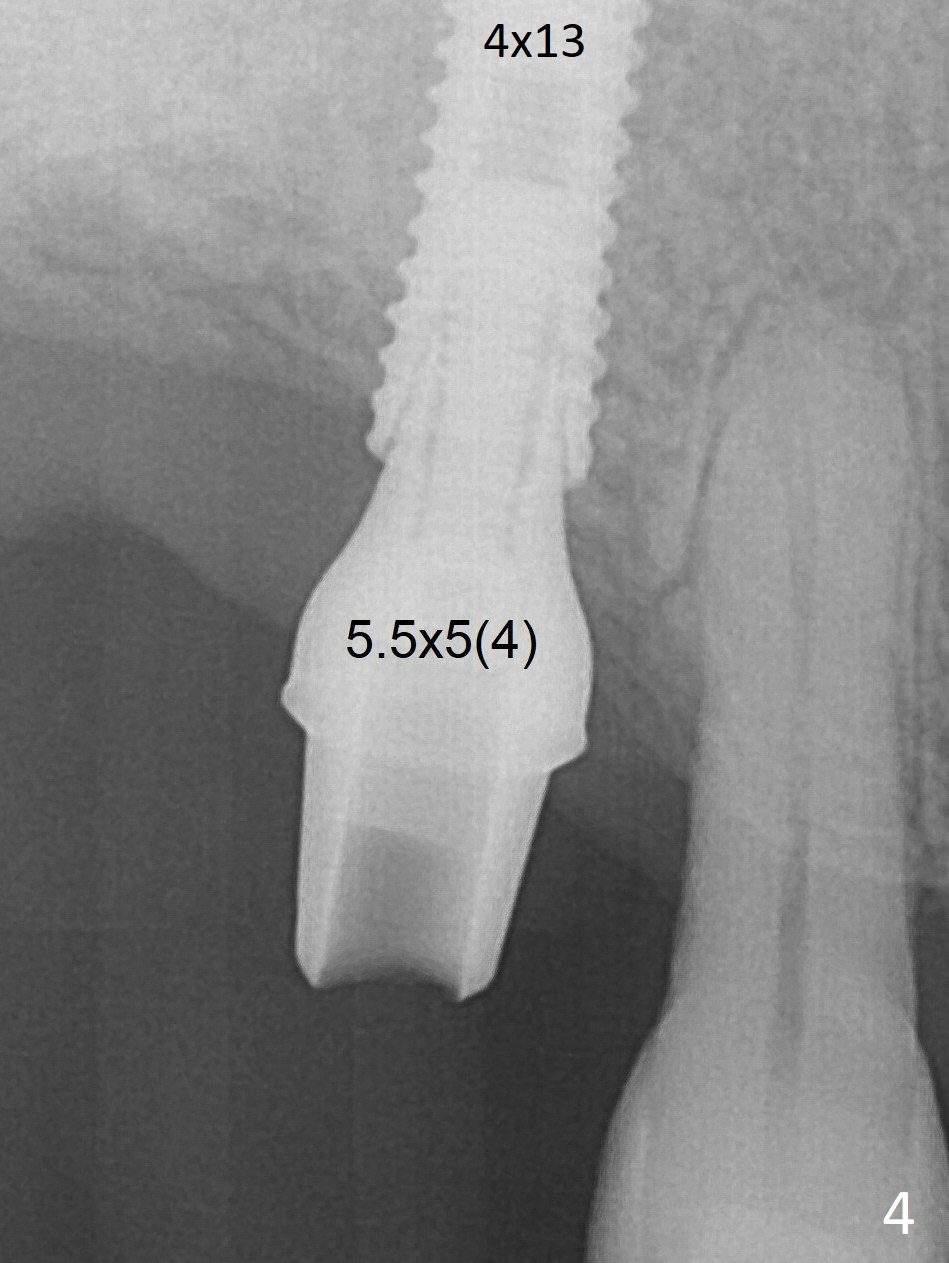

With further seating of the implant, a 5.5x5(4) mm abutment is used (Fig.4), which closes the access. No suture is warranted. An immediate provisional is fabricated for the patient's comfort and psychological effect. In fact, the abutment cuff changes to 5 mm prior to temporarization. There appears no bone loss <4 months postop (Fig.5). The margin is prepped except mesial prior to impression.